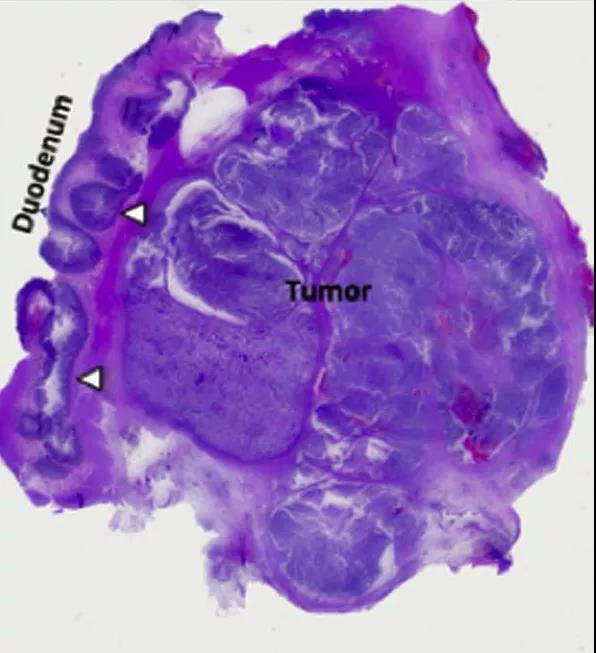

病理结果证实为:胰胆管型浸润癌(图 5)。

图 5 病理切片显示壶腹部肿瘤为胰胆管型,侵犯十二指肠

壶腹癌可能遵循「腺瘤-上皮内瘤变-局部恶变-腺癌」这一转化过程。根据腺癌的来源,壶腹部腺癌分为「肠型」和「胰胆管型」两类,主要区别如下:

1. 肠型腺癌起源于十二指肠粘膜,胰胆管型腺癌则起源于胰胆管上皮,特点是有乳头状突起伴散在纤维化,胞质清晰。